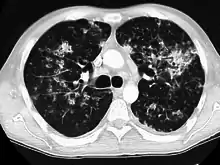

- CT showing diffuse ground-glass opacities in periphery of both lungs in patient with COVID-19.

COVID-19

Ground-glass opacity is among the most common imaging findings in patients with confirmed COVID-19.[16][17] One systematic review found that among patients with COVID-19 and abnormal lung findings on CT, greater than 80% had GGOs, with greater than 50% having mixed GGOs and consolidation.[16] GGOs with mixed consolidation has most often been found in elderly populations.[18] Several studies have described a pattern among initial, intermediate, and hospital discharge imaging findings in the disease course of COVID-19. Most commonly, initial CT imaging reveals bilateral GGOs at the periphery of the lungs. During initial stages, this is most often found in the lower lobes, although involvement of the upper lobes and right middle lobe has also been reported early in the disease course.[16][18] This is in contrast to the two similar coronaviruses, SARS and MERS, which more commonly involve only one lung on initial imaging.[19][20] As the COVID-19 infection progresses, GGOs typically become more diffuse and often progress to consolidation.[11][18] This is sometimes accompanied by the development of a crazy paving pattern and interlobular septal thickening.[18] In many cases the most severe pulmonary CT abnormalities occurred within 2 weeks after symptoms began.[17] At this point, many individuals begin showing resolution of consolidation and GGOs as symptoms improve. However, some patients have worsening symptoms and imaging findings, with further increase in septal thickening, GGOs, and consolidation. These patients may develop lung "white-out" with progression to acute respiratory distress syndrome (ARDS) requiring treatment escalation.[17][21]

Preliminary reports have shown many patients have residual GGOs at time of discharge from the hospital. Due to the novelty of COVID-19, large studies investigating the long-term pulmonary CT changes have yet to be completed. However, long-term pulmonary changes have been seen in patients after recovery from SARS and MERS, suggesting the possibility of similar long-term complications in patients who have recovered from acute COVID-19 infection.[22]